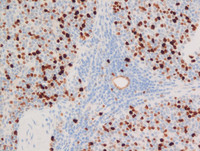

Figure 3 Immunostains LEF1, cyclin D1, Ki67, p53, bcl2

Ki67 immunostain (middle left image) at high power view showing 30-40% proliferation index.

P53 immunostain (middle right image) at high power view showing positive nuclear staining in all lymphoma cells.